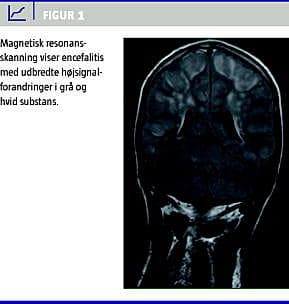

II. En 25-årig mand, der var nyretransplanteret i 2001, blev indlagt akut på mistanke om influenza A (H1N1)v med et døgns anamnese med tiltagende led- og muskelsmerter, febrilia, hovedpine, kvalme og opkastninger. Han var ikke influenzavaccineret. Den vanlige medicin omfattede ciclosporin, mycopheno-latmofetil, prednisolon og alfacalcidol. Ved indlæggelsen var han febril, vågen, klar og orienteret, og havde ikke NRS. Biokemi med C-reaktivt protein < 10, normale leukocytter og trombocytter. Kreatinin var 260 mikromol/l (habituelt niveau på 230 mikromol/l). Røntgen af thorax var normal. Oseltamivir 75 mg daglig påbegyndtes (dosisreduktion svarende til nyrefunktionen). Han klagede over vedvarende hovedpine. I løbet af dagen ændrede han psyke, udviklede cerebral konfusion, blev urolig og rodende. Han havde fortsat ikke NRS, men udviklede et universelt, tonisk krampeanfald, der kuperedes med intravenøst stesolid. CT af cerebrum var upåfaldende. CSV var normal (ingen pleocytose, normalt protein). PCR var negativ for herpes simplex-, varicella zoster- og enterovirus. MR-skanning af cerebrum viste encefalitisforandringer (Figur 1 ) i begge hemisfærer, cerebellum og pons. Der var positiv PCR for influenza A (H1N1)v i næsesvælgpodning, mens den var negativ i CSV. Patienten viste hurtig klinisk fremgang og kunne udskrives i habitualtilstand efter en uges indlæggelse.